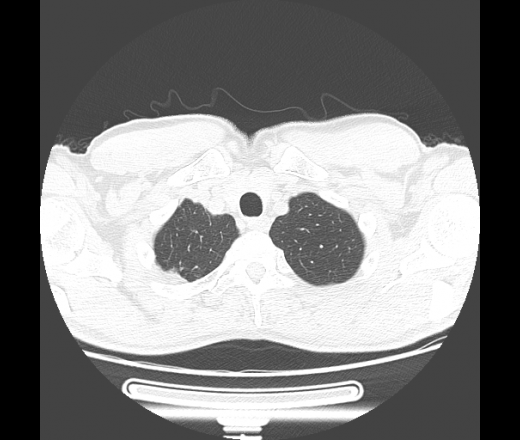

60 лет. В 1972 году верхнедолевая лобэктомия по поводу кавернозного туберкулеза.

Месяц назад появилась слабость, колящие боли под лопаткой, температура тела до 40 градусов, одышка. Вызывал скорую помощь, что-то делали, не помнит... Назначили АБ, на фоне лечения температура 40 днем, 38 вечером держалась неделю, потом постепенно становилось лучше...

Сейчас кашель, желтоватая мокрота, бывали с примесью крови. Температура сейчас ближе к норме.

Направлен с диагнозом: внебольничная субтотальная пневмония, осложненная сухим абсцессом? туберкулез?

С учётом всёй имеющейся информации, больше данных за абсцедирующую пневмонию. Подобная "сухая" полость, довольно нехарактерна для банальных пневмоний, а так же с учётом перенесённого туберкулёза в анамнезе, последний никак нелья исключать из дифряда. Можно сказать, что полость по скиологии очень похожа на симтом "перстня "- признак периферического рака, не исключается вариант сочетания последнего с пневмонией. И как всегда...перед нами встают три "кита"-пневмония, туберкулёз и рак!

Нужны все рентгенограммы, все анализы мокроты - хоть какое-то подспорье. Я бы написала так: с учетом отсутствия (не увидела) очагов отсева, лимфангита, более вероятен исход абсцесса в сухую полость, диф.диагноз с тбс и полостной формой рака. Думаю, что только оперативное лечение и последующая гистология даст верный ответ.

"Грибы" не стоит исключать из диф ряда. Но всё-таки стенки ен такие и тонкие, есть специфические локальные утолщения, виден симптом "перстня", наличие матовости дистальнее, более вероятно, полостная форма периферического рака. А грибы присоединились позже. Когда последний раз флюорографию проходил?

Полостная форма грибов - редкость..., особенно при актиномикозе. А при аспергиллезе - одна полость? и такая температура? Если думать про аспергиллез, то уж о поселении его в существующей полости... Но как-то не впечатляет! Хочется всё свести к острой инфекционной деструкции и формированию сухого абсцесса... Но откуда участки матового стекла нарисовались + в противоположном легком?

Единственное, что до сих пор смущает - лобэктомия. Что-то не сильно выражено ремоделирование правого лёгкого при резекции такого объёма ткани. И не даёт покоя междолевая плевра справа на сагиттальном скане - похоже, главная...

Лобэктомии тоже не заметил, но здесь есть еще бронх справа, который отходит до бифуркации. Тут максимум нет одного сегмента. В заключении обтекаемо написал что более вероятно дренированному абсцессу вследствие деструктивной пневмонии, либо полости с грибами. По клинике и лаборатории посмотрел еще когда поступал - практически ИТШок.

Я бы на первое место поставил абсцесс, но не стал бы исключать полостную форму рака. Хотя яркая клиника склоняет к первому. На туберкулез не очень-то похоже.